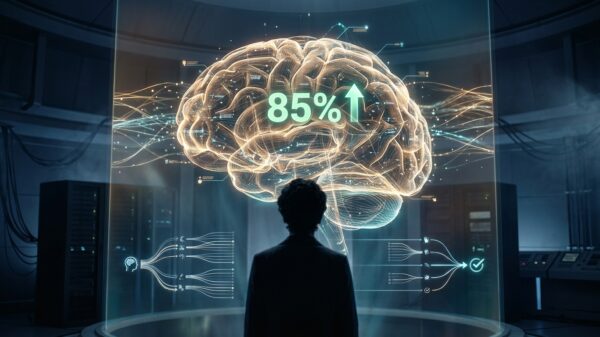

AI Generative

Generative AI achieves over 85% accuracy in predicting mental health treatment success, marking a pivotal shift toward Precision Psychiatry with $10 billion market potential...